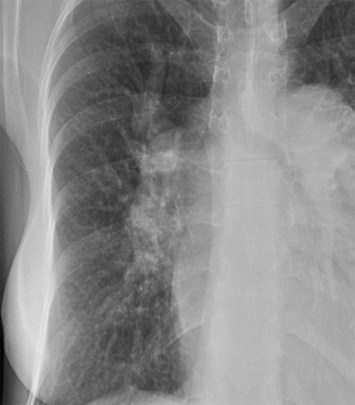

SIGNO DE LA CONVERGENCIA HILIAR

Signo visible en la radiografía de tórax que permite la diferenciación entre crecimiento hiliar causado por aumento del tamaño de los vasos del originado por una masa mediastínica yuxtahiliar. La convergencia de las imágenes vasculares hacia el hilio aumentado indica que éste corresponde a la arteria pulmonar aumentada de tamaño. En la imagen vemos un aumento de tamaño vascular del hilio derecho. Los vasos convergen hacia la arteria pulmonar.

Si los vasos no se dirigen hacia la lesión, el hallazgo sugiere que ésta se trata de una masa mediastínica (signo de la convergencia hiliar negativo).